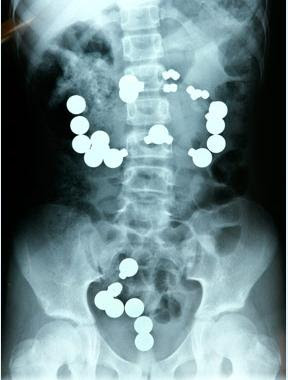

4. Gadis Cina yang Menyedihkan

X-ray dari Luo Cuifen, seorang gadis Cina berusia 29 tahun yang ditemukan memiliki 23 jahit jarum dalam tubuhnya. Cui fen mengeluh tentang darah di urin ,akhir 2007 dan ketika dokter melakukan x-ray-nya, menemukan jarum jahit mengambang dan tersebar di tubuhnya, itu menancap di ginjal, hati, paru-paru dan organ vital lainnya. Telah ada spekulasi bahwa jarum dimasukkan ketika dia masih bayi, karena beberapa jarum sudah patah berkeping-keping. Dia mengatakan bahwa kakek-neneknya pasti yang bertanggung jawab atas hal ini karena mereka mengharapkan anak laki-laki ketika ia dilahirkan. Namun ini tidak akan pernah bisa dikonfirmasi karena kedua-duanya kakek-neneknya meninggal. Perasaannya pasti terluka mengetahui hal ini ...